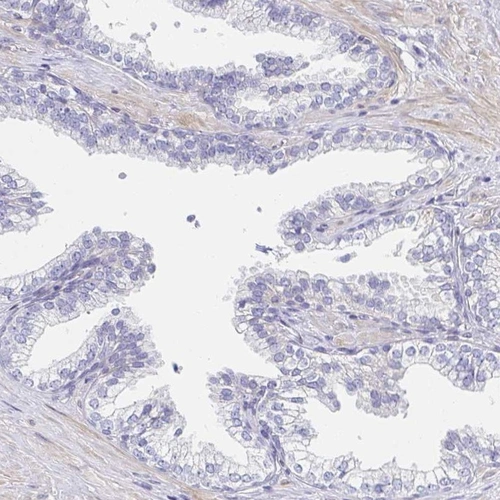

Immunohistochemistry analysis in human fallopian tube and prostate tissues using Anti-AKAP14 antibody. Corresponding AKAP14 RNA-seq data are presented for the same tissues.